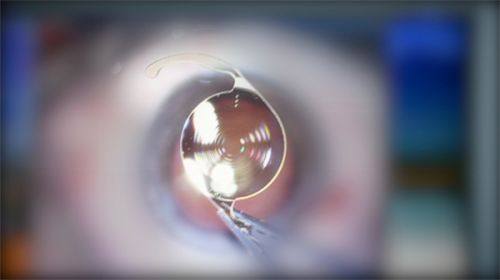

3. 优质视觉功能训练及近视矫正手术:优质视觉功能训练可以提高患者的视觉敏锐度、调节能力和双眼协调能力等。杨筱曦医生会根据患者的具体情况制定个性化的训练方案,通过一系列的训练方法,帮助患者改善视觉功能。对于想要摆脱眼镜的近视患者,她会进行全方面的术前评估,选择合适的近视矫正手术方式,如准分子激光手术、飞秒激光手术等,确保手术的安心和有效性。

5. 常见眼病诊疗:杨筱曦医生熟练掌握白内障、青光眼、糖尿病性视网膜病、黄斑病变等眼病的诊疗。对于白内障患者,她会根据患者的病情和身体状况,选择合适的手术时机和手术方式,帮助患者修复视力。对于青光眼患者,她会采取药物治疗、激光治疗或手术治疗等方法,控制眼压,保护视功能。对于糖尿病性视网膜病和黄斑病变等疾病,她会进行详细的眼底检查,制定个性化的治疗方案,延缓病情的发展。